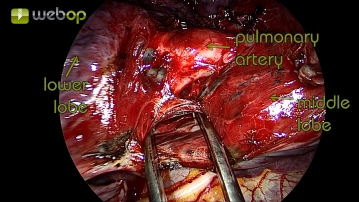

Präparation der Mittellappenvene

Nach Darstellung der Pulmonalarterie und Resektion der Parenchymbrücken erfolgt jetzt die Präparation am Lungenhilus. Die obere Lungenvene zeigt sich im Situs bereits ohne weitere Präparation. Für gewöhnlich drainiert die Mittellappenvene in die obere Lungenvene und kann dort eindeutig identifziert werden. Der Verschluss erfolgt hier mittels TitanClips.